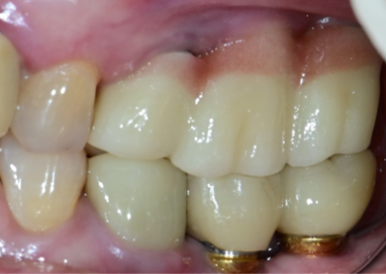

📍 실사례: “왼쪽 위가 계속 아파요… 다시 해야 할까요?”

최근 한 환자분이

“왼쪽 위 임플란트가 계속 불편하고 아파요”

라고 내원하셨습니다.

엑스레이와 구강 사진을 확인해보니,

- 보철물이 과도하게 볼록한 형태

- 치간공극이 닫혀 있어 세정 불가

- 잇몸 안쪽에 플라그 다량 축적

이런 구조는 아무리 양치를 잘 해도

청결 유지가 어렵고, 결국 잇몸 염증을 유발합니다.